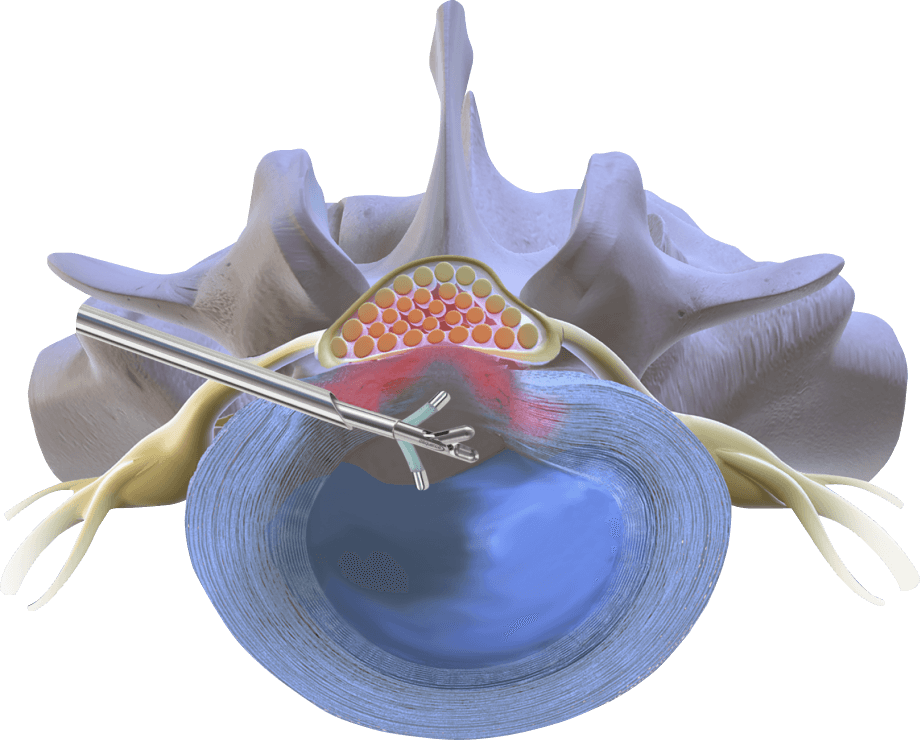

Радиочастотная Disc-FX дискэктомия —

по-настоящему малоинвазивная методика в лечении протрузии межпозвонкового диска

Чрескожный заднелатеральный

доступ через канюлю диаметром

3,0 миллиметра

Стандартная механическая

нуклеотомия с использованием

миниатюрных кусачек

Управляемый, гнущийся электрод — точная локализация радиочастотного воздействия на пульпозное ядро и фиброзное кольцо

Техника выполнения процедуры

Под контролем флюороскопии, эндоскопия опционально

Под местной анестезией плюс седация

Стандартная нуклеотомия кусачками — контроль удаляемого объёма у врача

В зависимости от задачи дозируется мощность радиочастотного воздействия: аблация ядра — высокая, констрикция фиброзного кольца — средняя

Положение пациента на животе или на боку при доступе на поясничном уровне

Чрескожный заднелатеральный доступ на поясничном уровне, передний доступ на шейном уровне

В ходе вмешательства последовательно выполняются три лечебные манипуляции

Нуклеотомия

Нуклеопластика

Аннулопластика